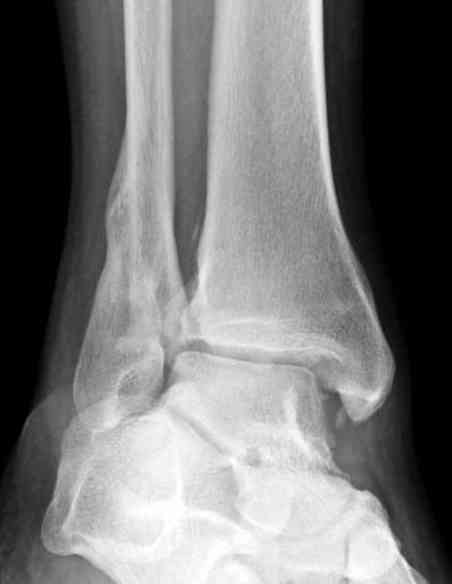

Мне кажется есть все основания попытаться сделать остеосинтез. Боль вследствие нестабильности. Нестабильность вследствие неанатомичного положения дистального отломка малоберцовой кости. Через 1,5 вполне возможно разобщить, репонировать и фиксировать длинный косой перелом наружной лодыжки. Вероятно, одновременно придется делать медиальный доступ для мобилизации внутренней лодыжки. Мы оперируем таких пациентов, функциональные (объем движений) результаты конечно хуже по сравнению с теми кого оперируем в первые 5-10 дней, но вполне удовлетворительные.

Согласен, на предоставленных рентгенограммах все основания для проведения открытого остеосинтеза.

сроки действительно небольшие, но если мы его и возьмем, то пройдет еще минимум неделя, кроме того смущает впечатление сращения н/лодыжки, похоже, что придется не разобщать,а остеотомировать, формирование оссификатов в полости сустава с медиальной стороны, да и сам пациент 1,5 месяца по поводу своей травмы сильно не напрягался

Здравствуйте, Максим! Мое мнение - оперировать, вот только срок после травмы определяет последовательность оперативных действий. В свежем случае при таком повреждении операция начинается с репозиции и синтеза наружной лодыжки, затем - вмешательство на внутренней стороне. В данном случае ригидность тканей может не позволить Вам, начав операцию снаружи, произвести адекватную репозицию. Мы в таких случаях поступаем следующим образом: начинаем с внутреннего доступа, из которого производим мобилизацию внутренней лодыжки. Затем из наружного доступа выполняем мобилизацию перелома наружной лодыжки. После этого достигается мобильность, характерная для свежего перелома. Синтез производим в последовательности: наружная сторона, синдесмоз (при необходимости), внутренняя сторона. 6 недель - не критический срок. Удавалось восстановить повреждения 3-4 месячной давности с хорошими функциональными результатами. А почему больных с такими сроками после травмы очень много - совсем другой вопрос. Кстати, почти наверняка сращения еще нет. Удачи! Константин Деданов, Челябинск, Областная больница